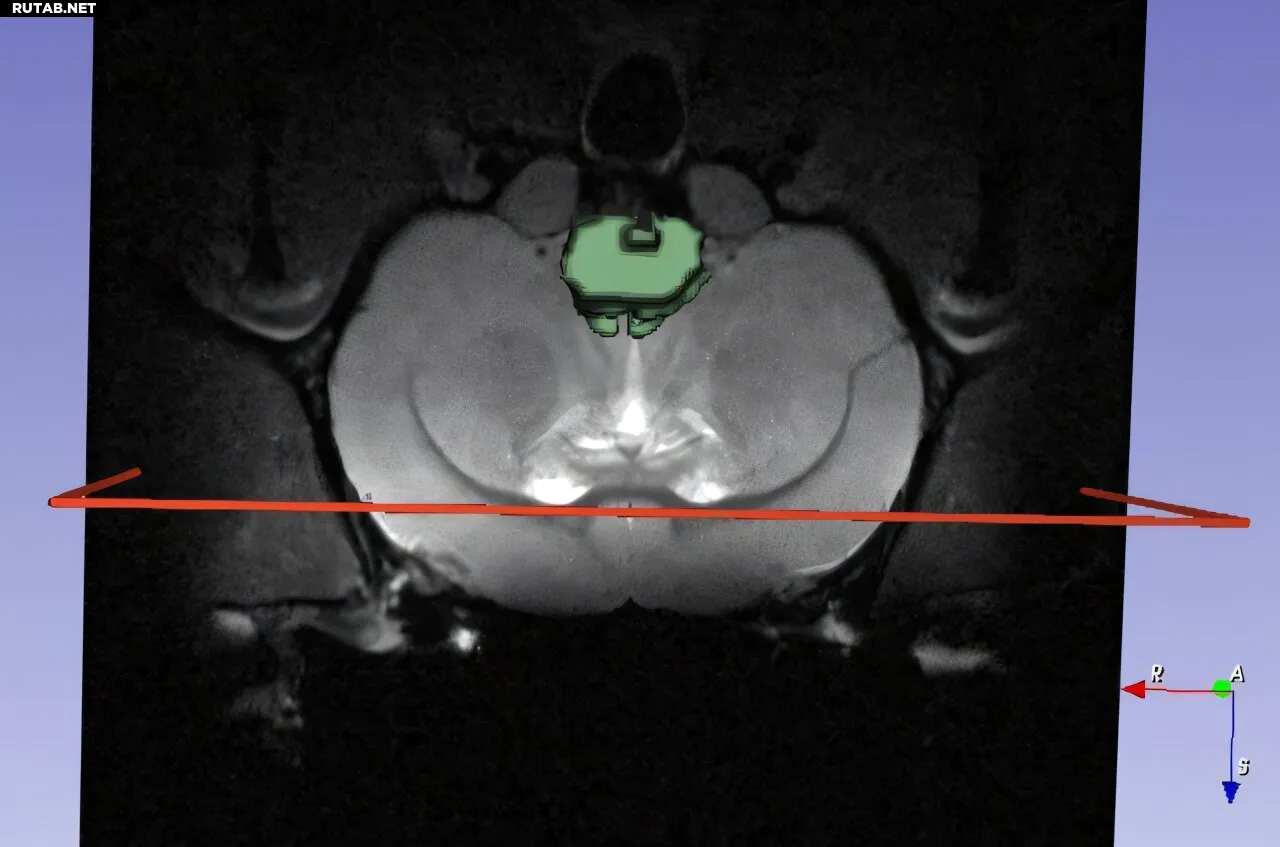

3D-сегментация МРТ-изображения мозга крысы. Автор: Джейсон Дживанандам

Ключевым элементом нового подхода стало сочетание молекулярной визуализации (МРТ, ПЭТ) с алгоритмами машинного обучения. Это позволяет отслеживать, «куда направляются нанопрепараты, какое количество достигает целевой ткани и какой биологический эффект это оказывает».